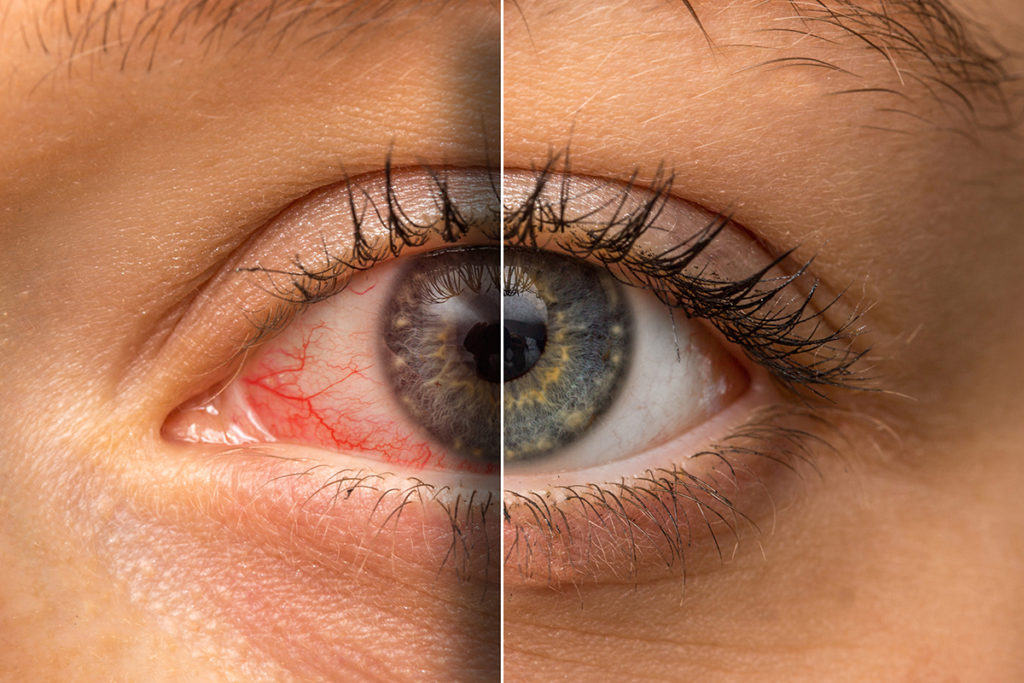

Obsah: Čo sú očné alergie? Aké sú príznaky očných alergií? Aké sú rozdiely medzi očnými alergia...

Obsah: Príznaky suchých očí Prečo používať kokosový olej na suché oči? Čo hovorí výskum A...